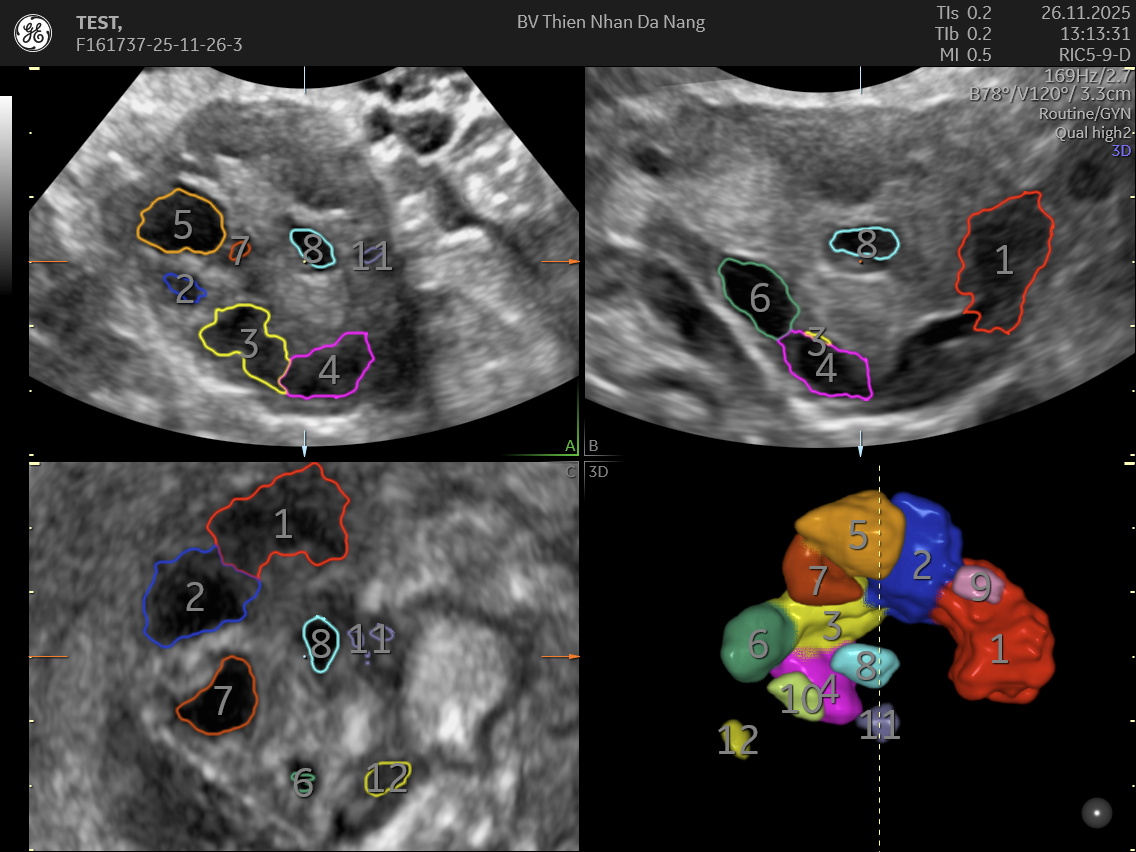

SIÊU ÂM 4D ĐẾM NANG BUỒNG TRỨNG: CÔNG NGHỆ GIÚP ĐÁNH GIÁ NANG (AFC) BUỒNG TRỨNG HIỆU QUẢ

Siêu âm 4D đếm nang buồng trứng là phương pháp hiện đại trong phụ khoa, giúp quan sát chi tiết cấu trúc buồng trứng từ nhiều góc độ và theo thời gian thực. Nhờ khả năng tái tạo hình ảnh sống động và chính xác, kỹ thuật này hỗ trợ đánh giá số lượng và kích thước nang buồng trứng, từ đó cung cấp dữ liệu quan trọng để đánh giá dự trữ buồng trứng, hỗ trợ thụ thai và điều trị hiếm muộn. So với siêu âm 2D truyền thống, siêu âm 4D giảm sai số, quan sát toàn bộ buồng trứng trong một lần quét và phân biệt nang trứng (AFC) và ảnh giả hiệu quả hơn.

Siêu âm 4D hỗ trợ đếm nang buồng trứng là phiên bản nâng cao của siêu âm 2D- 3D, cung cấp hình ảnh 3 chiều động theo thời gian thực. Khi ứng dụng trong phụ khoa, kỹ thuật này cung cấp hình ảnh buồng trứng rõ nét đến từng chi tiết, hỗ trợ bác sĩ:

Nhờ hình ảnh trực quan, siêu âm 4D giúp giảm thiểu sai số trong việc đếm nang – một trong những yếu tố quan trọng để đánh giá dự trữ buồng trứng và khả năng sinh sản của phụ nữ.

Khác với siêu âm 2D, siêu âm 4D mang lại hình ảnh chi tiết, sống động và cho phép bác sĩ xoay, phóng to hoặc thu nhỏ vùng buồng trứng. Phương pháp này giúp nhận diện chính xác từng nang, cấu trúc bên trong và mức độ tưới máu. Đây cũng là công cụ quan trọng để phát hiện u nang buồng trứng, nang lạc nội mạc.

Siêu âm 4D trong phụ khoa tại Thiện Nhân

Tại Thiện Nhân, kỹ thuật siêu âm 4D đếm nang buồng trứng được thực hiện bằng hệ thống Voluson Expert 22 (GE Healthcare – Mỹ), mang đến hình ảnh buồng trứng sắc nét với độ phân giải cao. Công nghệ UltraHD, HDlive và đầu dò âm đạo 3D giúp bác sĩ quan sát rõ từng nang, đánh giá chính xác số lượng, kích thước và cấu trúc nang noãn. Nhờ khả năng tái tạo hình ảnh chi tiết và ổn định ngay cả ở khách hàng khó siêu âm, siêu âm 4D trở thành phương pháp tối ưu để theo dõi dự trữ buồng trứng, hỗ trợ điều trị hiếm muộn và phát hiện sớm các bất thường buồng trứng.